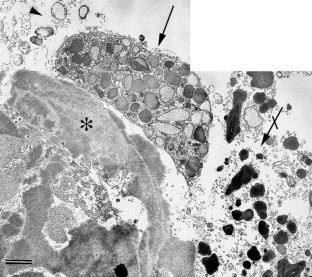

A 78-year-old woman with AFVD underwent MT with 360° retinotomy 3–4 months after loss of reading ability. Most of the vitelliform material was lost during surgery; the subfoveal tissue was excised, fixed in aldehydes, postfixed in reduced OsO4 and embedded in epoxy resin. Semithin sections were stained with toluidine blue for light microscopy (LM) and thin sections with uranyl acetate and lead citrate for transmission electron microscopy (TEM).

Postoperatively, the patient developed a retinal detachment complicated by proliferative vitreoretinopathy (PVR) requiring two additional vitreoretinal procedures before finally the silicone oil could be removed. Twenty-two months after MT the distance visual acuity was unchanged at 0.2; the near visual acuity had improved from less than 0.1 before MT to 0.4. The retina was completely attached. LM and TEM revealed serious alterations indicative of a breakdown of the outer layer of the retina.

Through the present single case it is not possible to determine whether MT could be a therapeutic approach in patients with AFVD. The most important cause for the limited postoperative visual improvement seems to be a primary injury of the foveal function due to the AFVD. This is supported by the extensive subfoveal degeneration and necrosis affecting not only the RPE cells but also their basement membrane and the interposed basal laminar deposits.